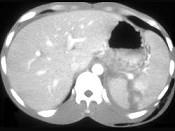

下列图像最佳诊断是 ( )A、脾破裂B、结肠破裂C、胰腺损伤D、小肠破裂E、肝破裂

问题 下列图像最佳诊断是 ( )

选项 A、脾破裂 B、结肠破裂 C、胰腺损伤 D、小肠破裂 E、肝破裂

答案 A